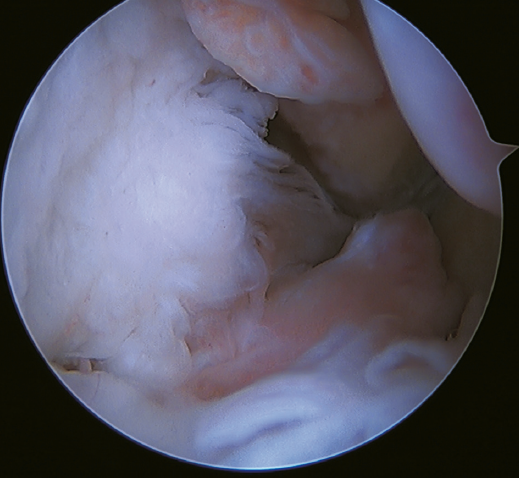

Rotational instability is a relatively novel concept introduced in 2011 by Buchhorn(67), describing combined injuries of the lateral complex and deltoid ligament, and an anatomical reconstruction technique for both injuries. Although there is no biomechanical evidence as to why medial injury occurs in patients who have not suffered eversion trauma, it is likely that the stress maintained on the medial complex in lateral instability may evolve into rotational instability - which is in line with the previously commented domino effect theory (5,62). It is estimated that up to 10-15% of all cases of CLAI may progress to injury of the medial complex, especially affecting its most anterior fibers. Recently, Vega(68) described the combination of injuries of the lateral complex with the "book-page" injury (Figure 7) of the superficial tibiotalar fascicle of the deltoid ligament, due to excessive internal rotation in chronic lateral instability, and its treatment through direct repair of both lesions. Acevedo(34) and Vega(68) also described the safety position of the anchors in the medial malleolus.

A recent consensus(64) recommends reconstruction of the ATFL and CFL (Figures 5 and 6) in cases of generalized laxity or when there is poor tissue quality. Other indications would be when there are doubts about subtalar stability or in patients with a ruptured CFL. For some authors, BMI > 30 kg/m2 would also be an indication for this technique.

In 2022, Ferkel(30) published the indications for reconstruction: failure of ligament repair, BMI > 30 kg/m2, cases of generalized laxity, athletes or workers with a high functional demand, and cases where poor tissue quality is observed intraoperatively. Another indication is when there is significant instability with a talar tilt angle difference of over 10° with respect to the contralateral ankle, or an absolute angle of more than15°. In the same paper, this author concluded that direct arthroscopic repair of the ATFL is an excellent technique in selected cases.